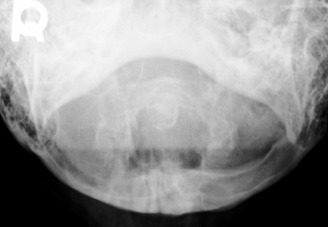

1. What is the key finding?

There are obvious degenerative changes of the cervical spine as well as osteopenia. The key finding however is the posterior subluxation of the atlas (C1) on the axis (C2). This is evident by the disruption of the spinolaminar line. The opacity with the sclerotic borders in the expected location of the dens represents the anterior arch of C1. Posterior to that you can make out the subtle appearance of a rounded opacity representing the dens, displaced posteriorly from the body of C2.

Diagnosis - Unstable Os Odontoideum